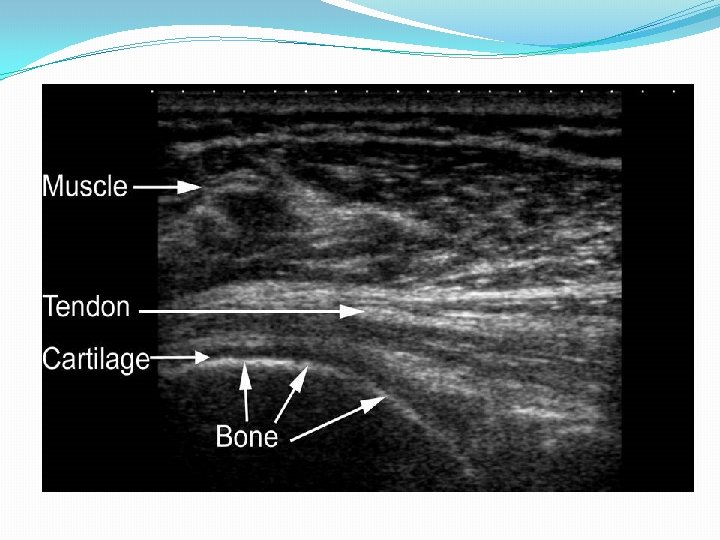

Purpose �Review common causes of Hemiplegic Shoulder Pain (HSP)- Focus on Post stroke �Diagnosis using PE and Imaging Studies �Introduce Musculoskeletal Ultrasound (MSK US) as an aid to diagnosis of HSP �Hands on demo �Please check out Sept 2013 Am L PM&R Ozcakar et al- Utility of MSK US in Rehab settings

HSP Summary �New tools such as MSK ultrasound may improve accuracy of HSP diagnosis �Bicipital tendinopathy/tenosynovitis more common than previously thought �Subscapularis tear more common than previously thought in chronic stage �Improved diagnosis can improve treatment

Hands on Demonstration �Kris Gellert OTR-Hands on Demo of OT eval and treatment of HSP �Anne Kirchmayer MD (FAAPMR Sports and Neuromuscular Med)- MSK US of biceps tendon and subscapularis �Andy Kirsteins MD- MSK of supraspinatus and infraspinatus